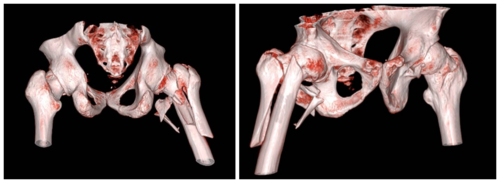

*CT三维重建

患处行CT三维重建后发现,骨折程度复杂,骨折类型为股骨大小转子均发生明显移位的Tronzo-Evans分型Ⅳ型粉碎性骨折,且骨折线累及股骨转子下。常规髓内针假体长度不足以维持复位后骨折端稳定,且患者多年强直性脊柱炎导致脊柱后凸畸形严重,无法保持平卧,术中卧位选择也是无法避免的一个难题。对于该患者手术卧位、手术方式以及假体选择,孟祥海专家团队充分进行术前讨论,最终决定使用加长柄髓内钉假体进行固定,并且对骨折断端复位后进行钛缆加强固定。10月9日,孟祥海副主任医师带领刘照睿副主任医师、张英副主任医师、杜闫圻医师顺利完成了右股骨转子间骨折闭合复位髓内钉内固定术,术后安返病房。